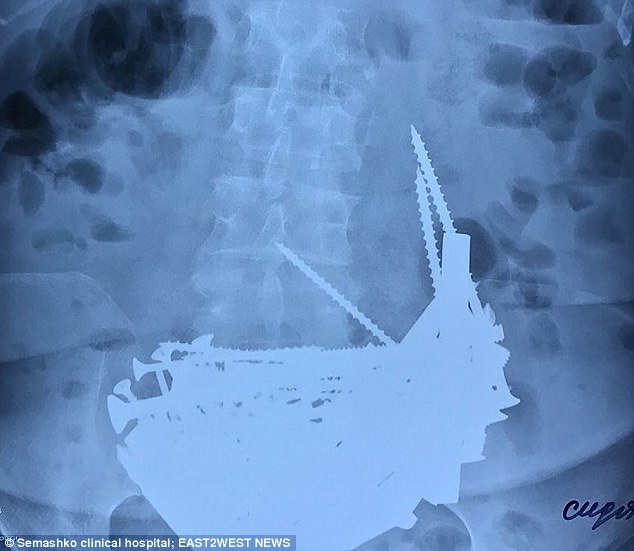

Hình ảnh phim chụp Xquang của bà Nina.

Sau khi chụp X quang, nhân viên y tế đã sốc khi phát hiện rất nhiều đồ vật bằng kim loại trong bụng và yêu cầu tiến hành phẫu thuật ngay lập tức. Cụ thể, các bác sĩ đã tìm thấy hơn 152 vật thể bao gồm cả đinh dài, ốc vít, bu lông, chốt cửa và một số phế liệu trong dạ dày rộng 15 cm của bà Nina.

Các đồ vật được lấy từ dạ dày của bà Nina hầu như đã bị han gỉ.